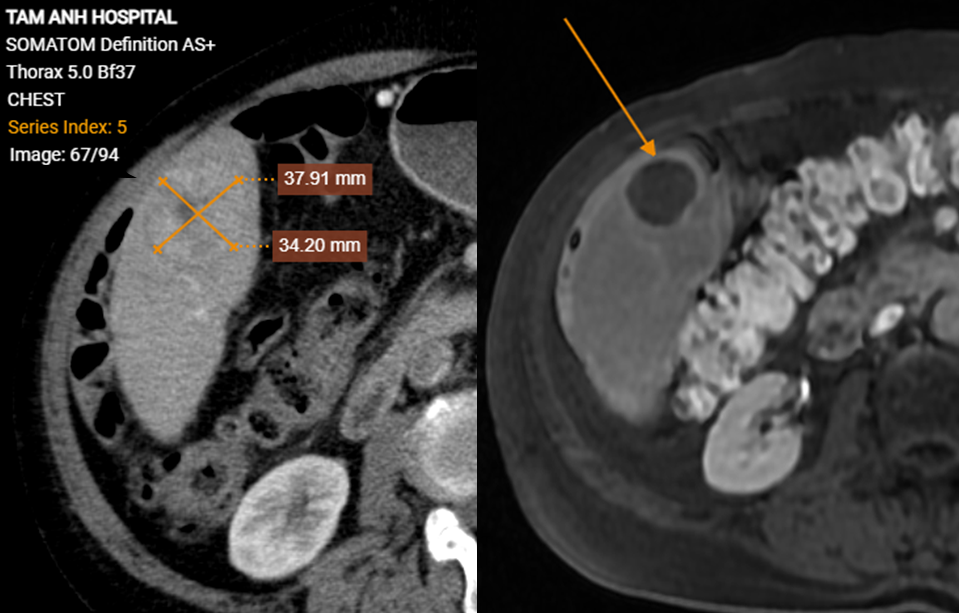

Mr. Phong's tumors were discovered during a routine cancer screening, despite him experiencing no unusual symptoms. His history of smoking for over 30 years, along with cirrhosis and hepatitis B virus infection, placed him at high risk. An ultrasound revealed a hypoechoic mass in his liver. Blood tests showed an AFP (alpha-fetoprotein) level exceeding 1440 ng/ml, over 200 times the normal threshold, a strong indicator of liver cancer. CT scans confirmed two liver tumors, measuring 15x20 mm and 37x34 mm. Additionally, he presented with thoracic aortic dissection, atherosclerosis, aneurysms in other aortic arteries, and 56% stenosis of the celiac artery origin.

Mr. Phong's liver tumor before (left) and after treatment, showing necrosis (right). Photo: Tam Anh General Hospital |

Mr. Phong's liver tumor before (left) and after treatment, showing necrosis (right). Photo: Tam Anh General Hospital

A follow-up MRI three months later showed a significant reduction in the size of both liver tumors. They no longer absorbed contrast, indicating that the cancer cells had necrotized. According to Dr. Hien, Mr. Phong's overall health improved, he gained weight, and his AFP level returned to a normal range of 6,5 ng/ml, signifying a complete response to the treatment.